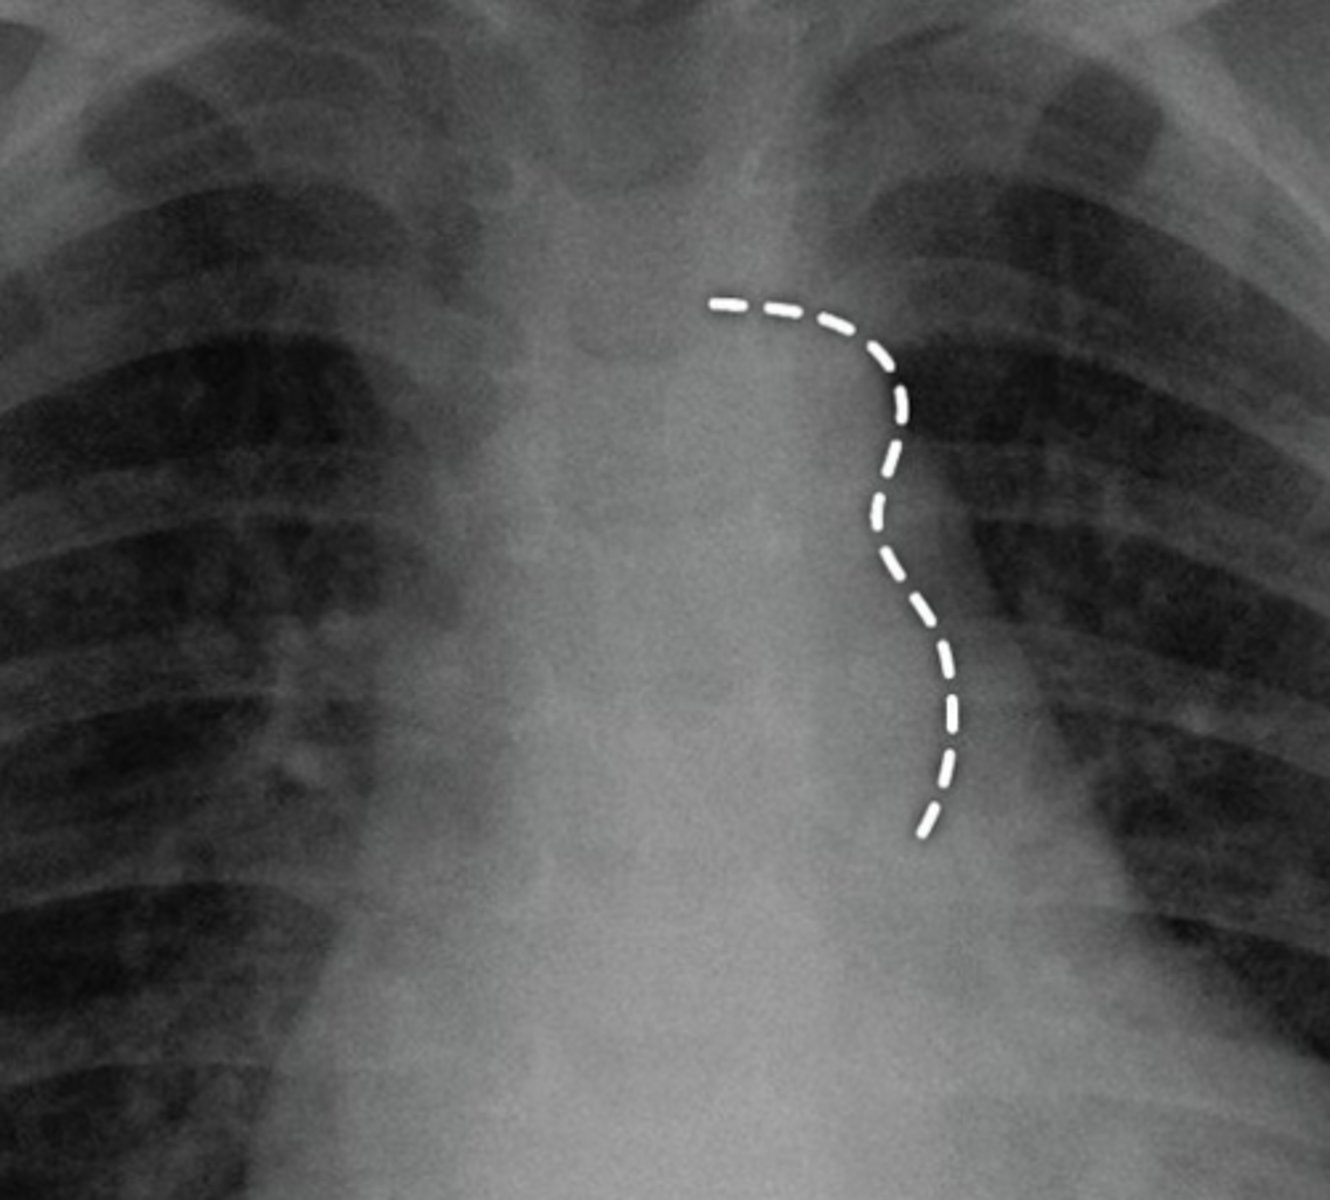

What is the chest radiograph finding in coarctation of the aorta?

Figure 3 sign.